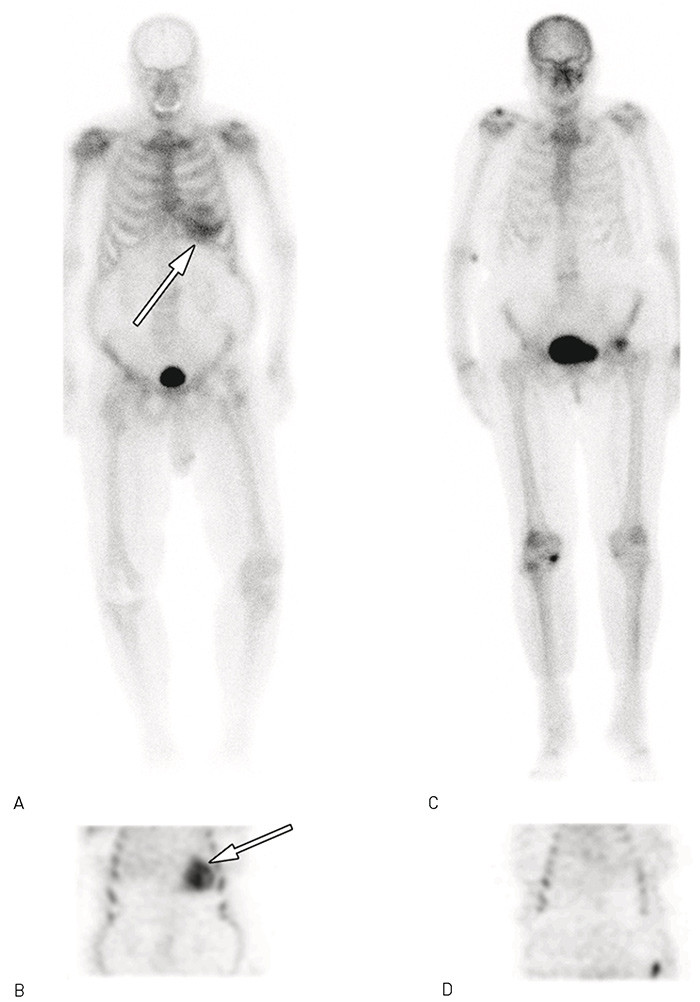

Serum-immunelektroforese og serumnivåer av lette immunglobulinkjeder var normale uten påvisbar monoklonal komponent, og det ble ikke funnet Bence Jones’ proteiner i urinen. Ut ifra disse funnene var det ikke holdepunkter for AL-amyloidose. Scintigrafi av pasienten med 99mTc-3,3-difosfono-1,2-propandikarboksylsyre (99mTc-DPD) viste allerede etter fem minutter høyt opptak i myokardet og fremdeles høyt opptak etter tre timer (fig 3). Disse funnene var forenlig med transtyretinrelatert hjerteamyloidose. Ut fra familieopplysninger var det ingen holdepunkter for at det skulle være en arvelig form for transtyretinrelatert hjerteamyloidose.

Forskjellige indikatorer er blitt brukt for scintigrafisk påvisning av amyloidose i forskjellige organer (2, 11). En nylig undersøkelse viste at scintigrafi med 99mTc-DPD påviste transtyretinrelatert hjerteamyloidose med meget høy sensitivitet og spesifisitet (11) (fig 3). Ved hjerteamyloidose av ulike former vil magnetisk resonans-undersøkelse typisk vise diffust forsterket senopptak av gadolinium i myokardet, mest uttalt subendokardialt (12, 13). Hjerteamyloidose kan histologisk bekreftes ved hjertebiopsi, og funn av amyloidnedslag i biopsier fra andre organer som rectum vil indirekte bekrefte diagnosen (2). Biopser fra ekstrakardiale organer har imidlertid lav sensitivitet for påvisning av transtyretinrelatert hjerteamyloidose (14). Nærmere undersøkelser (immunhistokjemiske analyser av amyloidet, DNA-analyser m.m.) kan vise hvilken type amyloidose som foreligger (2).

Påvisning av årsaker til hjertesvikt er viktig for valg av behandling og vurdering av prognose. Hos vår pasient var det sannsynligvis ikke arteriell hypertensjon som var utløsende årsak til progressiv hjertesvikt, slik man først hadde antatt. Derimot viste ekkokardiografi distinkte forandringer som ved hjerteamyloidose (fig 2). Den videre utredningen ga ikke holdepunkt for AL-amyloidose, mens scintigrafi med 99mTc-DPD viste myokardforandringer godt forenlig med transtyretinrelatert hjerteamyloidose (fig 3). Det forelå ikke familiær forekomst av hjertesvikt, og mest sannsynlig hadde pasienten den langt vanligere senile formen av transtyretinrelatert lidelse. Representative biopsier kunne tenkes å ha gitt ytterligere bekreftelse på sykdommen. Ekstrakardiale biopsier har imidlertid lav sensitivitet for transtyretinrelatert amyloidose. Å henvise vår pasient til universitetssykehus for å ta hjertebiopsi syntes unødvendig, ettersom funnene ved ekkokardiografi og scintigrafi gjorde oss sikre på diagnosen. Eventuelle funn ved hjertebiopsi ville neppe endret behandlingen hos denne syke pasienten.